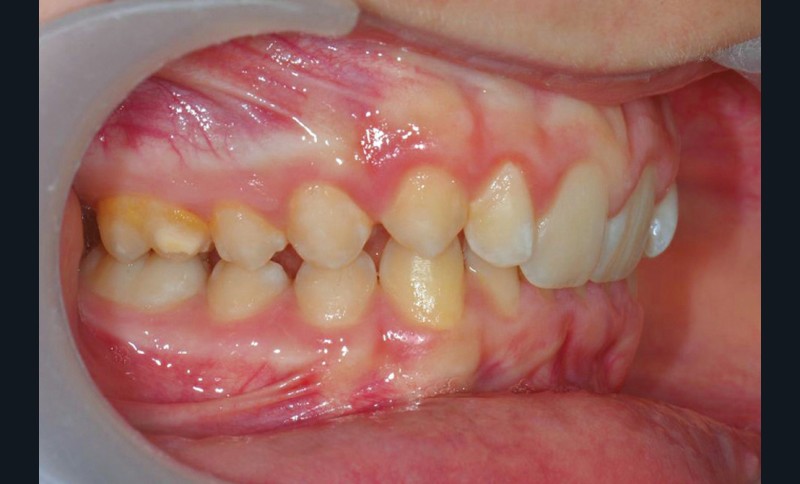

Son profil convexe s’inscrit dans un contexte de classe II squelettique par rétrognathie mandibulaire normodivergente sur un schéma de Classe II/2 avec supraclusion et encombrement modéré (fig. 1 à 7).

Le parodonte est de type 1 selon la classification de Maynard et Wilson.